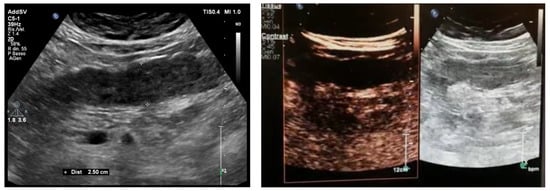

6.1. GIUS Signs of SBO

6.2. GIUS Signs of LBO

8.1. Non-Occlusive Mesenteric Ischemia

8.2. Acute Venous Mesenteric Ischemia

8.3. Ischemic Colitis